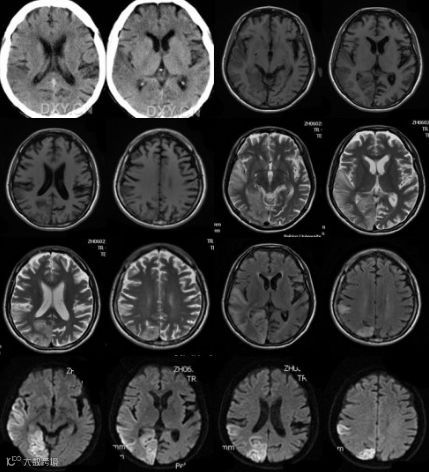

(1)在神经系统应用较为成熟。三维成像和流空效应使病变定位诊断更为准确,并可观察病变与血管的关系。对脑干、幕下区、枕大孔区、脊髓与椎间盘等的显示明显优于CT。对脑脱髓鞘疾病、多发性硬化、脑梗塞、脑与脊髓肿瘤、血肿等的诊断有较高价值。

脑部不同位置的MRI成像